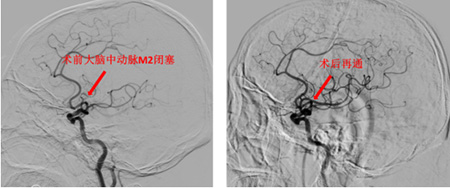

病例5——当血管再通后遇上出血,我们依然在守护:(60岁男性)因意识不清入院,静脉溶栓后意识仅轻微改善。检查发现左侧大脑中动脉闭塞,且脑组织已出现较大范围梗死。为挽救更多脑组织,经充分评估及家属同意,团队仍为其施行取栓术并成功实现血流通畅。术后次日,患者复查CT提示梗死区域发生了预期内的出血转化(symptomatic hemorrhagic transformation)。面对这一挑战,神经重症与神经外科团队立即启动应急预案,给予规范化治疗。目前出血已稳定,患者正在严密监护与综合治疗中稳步恢复。此病例深刻体现了卒中救治的复杂性与团队应对全程风险的完备能力。